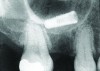

Implant related complications may be classified as minor, intermediate, major reversible/nonreversible, or major nonreversible. For example, a simple complication like a fractured abutment screw is usually considered a minor complication. It usually can be corrected with minimal cost, time, pain, and inconvenience. Treatment may be more involved for an intermediate complication such as a fractured implant (Figure 1). Up the severity scale are major complications, such as when an implant migrates into the sinus2 (Figure 2), or is exposed by mucosa and bone loss and visible to the patient a year after restoration (Figure 3 and Figure 4). Major complications may cause irreversible damage and/or require multiple procedures to try to make the patient “whole,” adding cost, time, pain, and surgeries (Figure 5 and Figure 6), and the patient may or may not receive the original restoration.

A fractured implant is classified as an intermediate complication

Figure 1